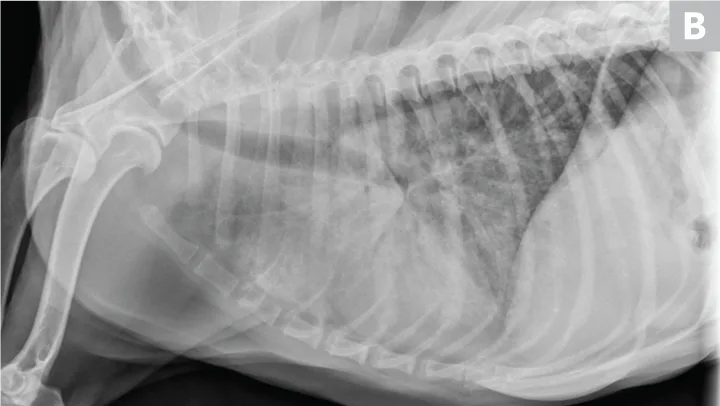

Pulmonary neoplasia may, on occasion, have a more diffuse nature. This is common with pulmonary lymphoma40 and is sometimes seen with carcinoma (author experience). Pulmonary lymphoma can have a rapid clinical course and mimic acute disorders. A diffuse, unstructured interstitial pattern is typically appreciated. Additionally, bronchointerstitial, alveolar, and nodular patterns may be observed (Figure 7).40

FIGURE 7

(A) Pulmonary lymphoma with a diffuse, patchy bronchointerstitial pattern confirmed on bronchoalveolar lavage and peripheral lymph node aspiration. (B) Pulmonary carcinoma with a diffuse, severe bronchointerstitial pattern confirmed on bronchoalveolar lavage and postmortem examination. Note: Pulmonary and hilar lymphadenopathy are not always present.